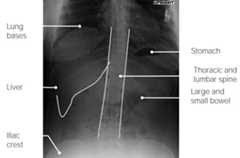

Normal abdominal radiograph

Normal abdominal radiograph (upright)

Image by Hetal Verma.